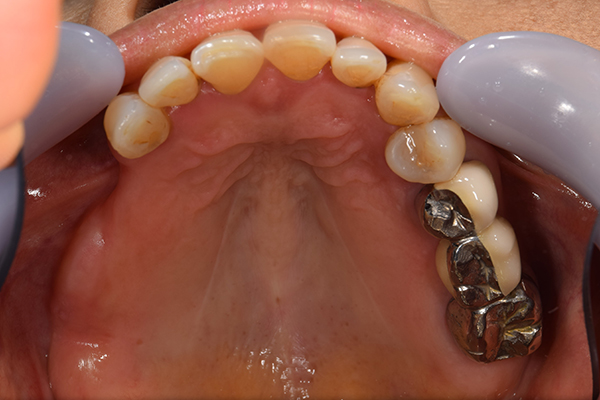

ケース3(インプラントを用いた部分入れ歯)

右上と左下の歯がない方です。 上の入れ歯の安定が悪く、作り直したいとのことでいらっしゃいました。 今お使いの上の入れ歯を見てみると、口蓋部分が抜けており、安定性に欠ける構造になっていました。この入れ歯はノンメタルクラスプデンチャーといって、金属のバネを使用しない 入れ歯になります。これは見た目は良いのですが、歯への負担が大きいことと、入れ歯自体がやわらかいため、噛むには不便なことがあります。

入れ歯は極力薄くするために金属を使用しました。しっかり噛める様にするため、ノンメタルクラスプデンチャーにはしませんでした。

上の入れ歯(表)

上の入れ歯(裏)

下の入れ歯

入れ歯を入れた状態のお口の中の写真です。バネも極力目立たないように作成しています。

年齢 70代・女性

主訴 上の入れ歯の安定が悪く、作り直したい

治療期間 5ヶ月

治療費 .診査診断:55,000円

.インプラント埋入:165,000円

.アバットメント:33,000円

.義歯:330,000円

治療方針 右片側のみ奥歯がない方です。

この様な場合入れ歯は反対側に維持を求めるため、大きな入れ歯になりがちです。

そのため違和感が強いことがおおいです。

また、片側だけないですので、安定もむずかしくなります。

そこで、安定をよくするために、右の奥歯の位置にインプラントをいれて、義歯が揺れない様にすることにしました。

治療内容 レントゲンをみて最低限の長さのインプラントを右上の奥歯の位置に埋入しました。インプラントと骨の結合(オッセオインテグレーション)と歯肉の治癒を待ち、アバットメントをいれて型取りをして、入れ歯を作成しました。極力薄くするために、金属をもちいた入れ歯にしました。

特記事項 インプラントは必ず成功するというものではありません。 また治癒も人それぞれで、長くかかることもあります。 入れ歯を入れ終わったあとも、アバットメントが緩んできたり、入れ歯が歯ぐきにあたって痛いところもでてきますので、調整は必要になります。